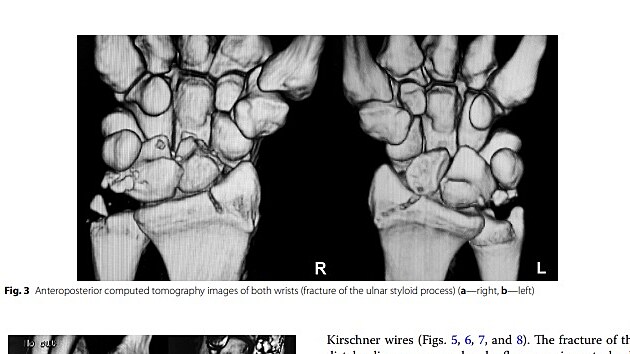

„Jedná se o raritní úraz, který nebyl dosud ve světové literatuře popsán. U pacienta, který spadl ze čtyřmetrového lešení, došlo ke zlomeninám a vykloubení obou zápěstí a vykloubení obou loketních kloubů,“ popsal operatér úrazu Jaroslav Pilný. Poraněný muž byl do nemocnice v Novém Městě na Moravě převezen z jiného zdravotnického zařízení.